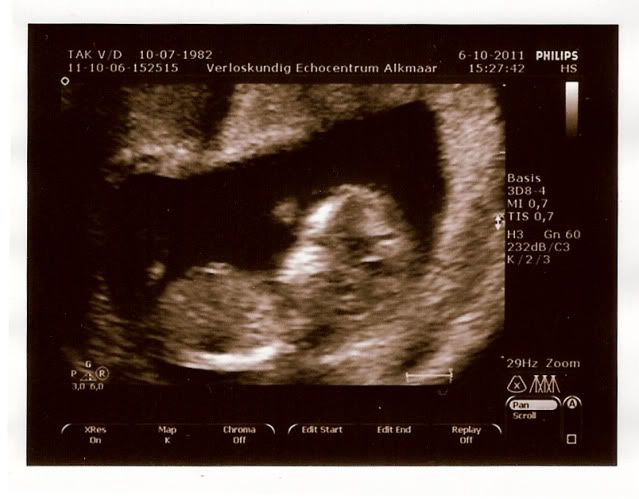

Nou meiden zwanger van een echt Kooijtje hoor hihihi ze zette het echo apparaat op mijn buik en hij/zij begon meteen driftig te boxen hahaha.

Mijn mama deed lachen om mijn grote voetjes!